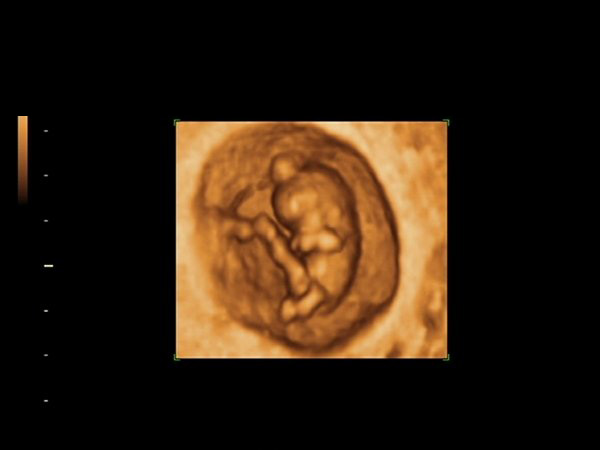

Har i dag været til scanning for første gang. (Lidt før tid - 10+1) og ville bare lige dele de dejlige billeder med jer. Den var meget livlig. Både ben og arme bevægede sig hele tiden

Er i den syvende himmel på sådan en dejlig solskinsdag